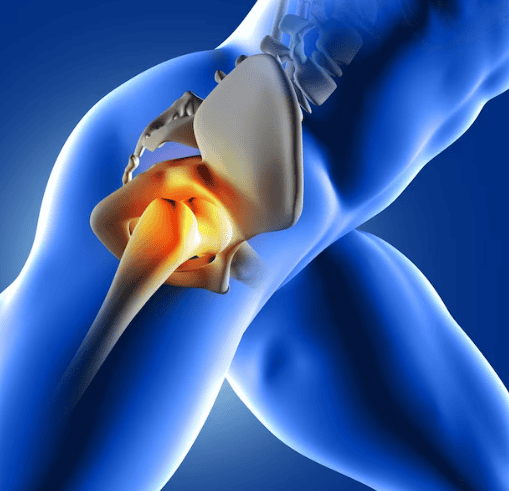

SI una cosa clara tenen els pacients sotmesos a una artroscòpia de maluc, és que el dolor després d’aquesta intervenció no se’n va i fins i tot pot reaparèixer. És el mateix que tenien abans d’operar-se.

Segurament que la cirurgia a la qual han estat sotmesos ha millorat l’estat del seu maluc, però el pacient té un dolor que no els hi permet fer la seva vida normal. Ni caminen amb normalitat, ni poden pujar costes, ni conduir massa estona, asseguts en un lloc una mica baix, no ho toleren, o quan comencen a córrer han d’aturar-se.

Problemes musculars que afecten la recuperació

És molt freqüent que no existeixi una lesió a l’articulació. La major part de les vegades són els músculs, els tendons que no arriben a tenir la suficient força o elasticitat per tornar a funcionar bé.

El psoes i el recte femoral, els músculs que flexionen el maluc, necessiten tenir tanta força com suficient elasticitat per generar un moviment i una potència que ens permeti pujar un escala. I són els mateixos músculs que durant mesos no han treballat normal perquè el dolor de maluc no els hi deixava estirar-se amb normalitat.

És freqüent que les primeres setmanes, mentre es va crosses i el nivell no és molt exigent, no es noten, però quant a deixem les crosses i demanem més treball al nostre maluc, aquests dolors tornen a aparèixer i es disparen.

Dolor a la zona del gluti major: causes i solucions

Altra zona on sovint es té dolor després d’una artroscòpia de maluc és en mig de la natja. Aquí és on està el gluti major. És el múscul que ens permet caminar, pujar escales, o ajupir-nos d’una cadira.

Quan hi ha problemes de maluc aquest múscul perd força i triga mesos a recuperar-se. Com aquestes activitats les iniciem de seguida i el ritme de recuperació muscular és més lent que la nostra progressió, apareix dolor al mig de la natja. Com un ganivet que es clava. S’ha de treballar el múscul perquè el dolor desaparegui.

¿Quan hem de preocupar-nos del dolor articular?

El dolor després d’una artroscòpia de maluc que hauria de preocupar-nos més seria el dolor persistent a l’engonal. Aquell dolor que ve des del maluc, des de l’articulació. Si es manté el dolor, a aquesta zona, podem tenir un problema per diverses causes.

La més preocupant és que la cirurgia hagi estat insuficient. Quan la cirurgia rebaixa us satura el làbrum (fibrocartílag que cobreix l’os acetabular) i el podem fer curt. La por de ser massa agressius els pot portar al fet que existeixen zones on no s’hagi resolt el pinçament. I com el làbrum pot patir les conseqüències, pot tornar-se a rompre, I això, a vegades obliga, a tornar a passar pel quiròfan.

Dolor a l’engonal: possibles complicacions i causes

Si el problema inicial no fos solament el pinçament i tinguem un cert grau d’artrosi, la rigidesa associada pot empitjorar i totes les estructures de parts toves poden reduir-nos la mobilitat del maluc i augmentar el dolor.

Malgrat que hi hagi un aspecte radiològic bo, el dolor i la falta de mobilitat poden portar-nos a fer altra cirurgia. En aquest cas, podem plantejar-nos repetir l’artroscòpia o fins i tot canviar a una pròtesi de maluc.

Quan optar per una segona intervenció

Quan el dolor després d’una artroscòpia de maluc, persisteix, és clar que aquesta cirurgia no va ser la millor solució. Sobretot, si la nova cirurgia es planteja a menys de dos anys després de l’artroscòpia. En moltes ocasions és obvi que els pacients no milloraran amb una artroscòpia i es decideix directament a una pròtesi de maluc.

Però no sempre és tan fàcil. Pacients joves, amb un lleu desgast, alguns canvis degeneratius, poden fer-nos dubtar si encara podem ajudar-los amb una tècnica que conservi el seu maluc o directament optar per una major agressivitat, sacrificar el seu maluc i entrar en el món de les pròtesis de maluc.

Beneficis i riscos d’una pròtesi de maluc

Com veurem més endavant, la pròtesi de maluc no és la solució definitiva i totalment segura, sinó que tenim uns problemes que afortunadament són poc freqüents però devastadors pels pacients.